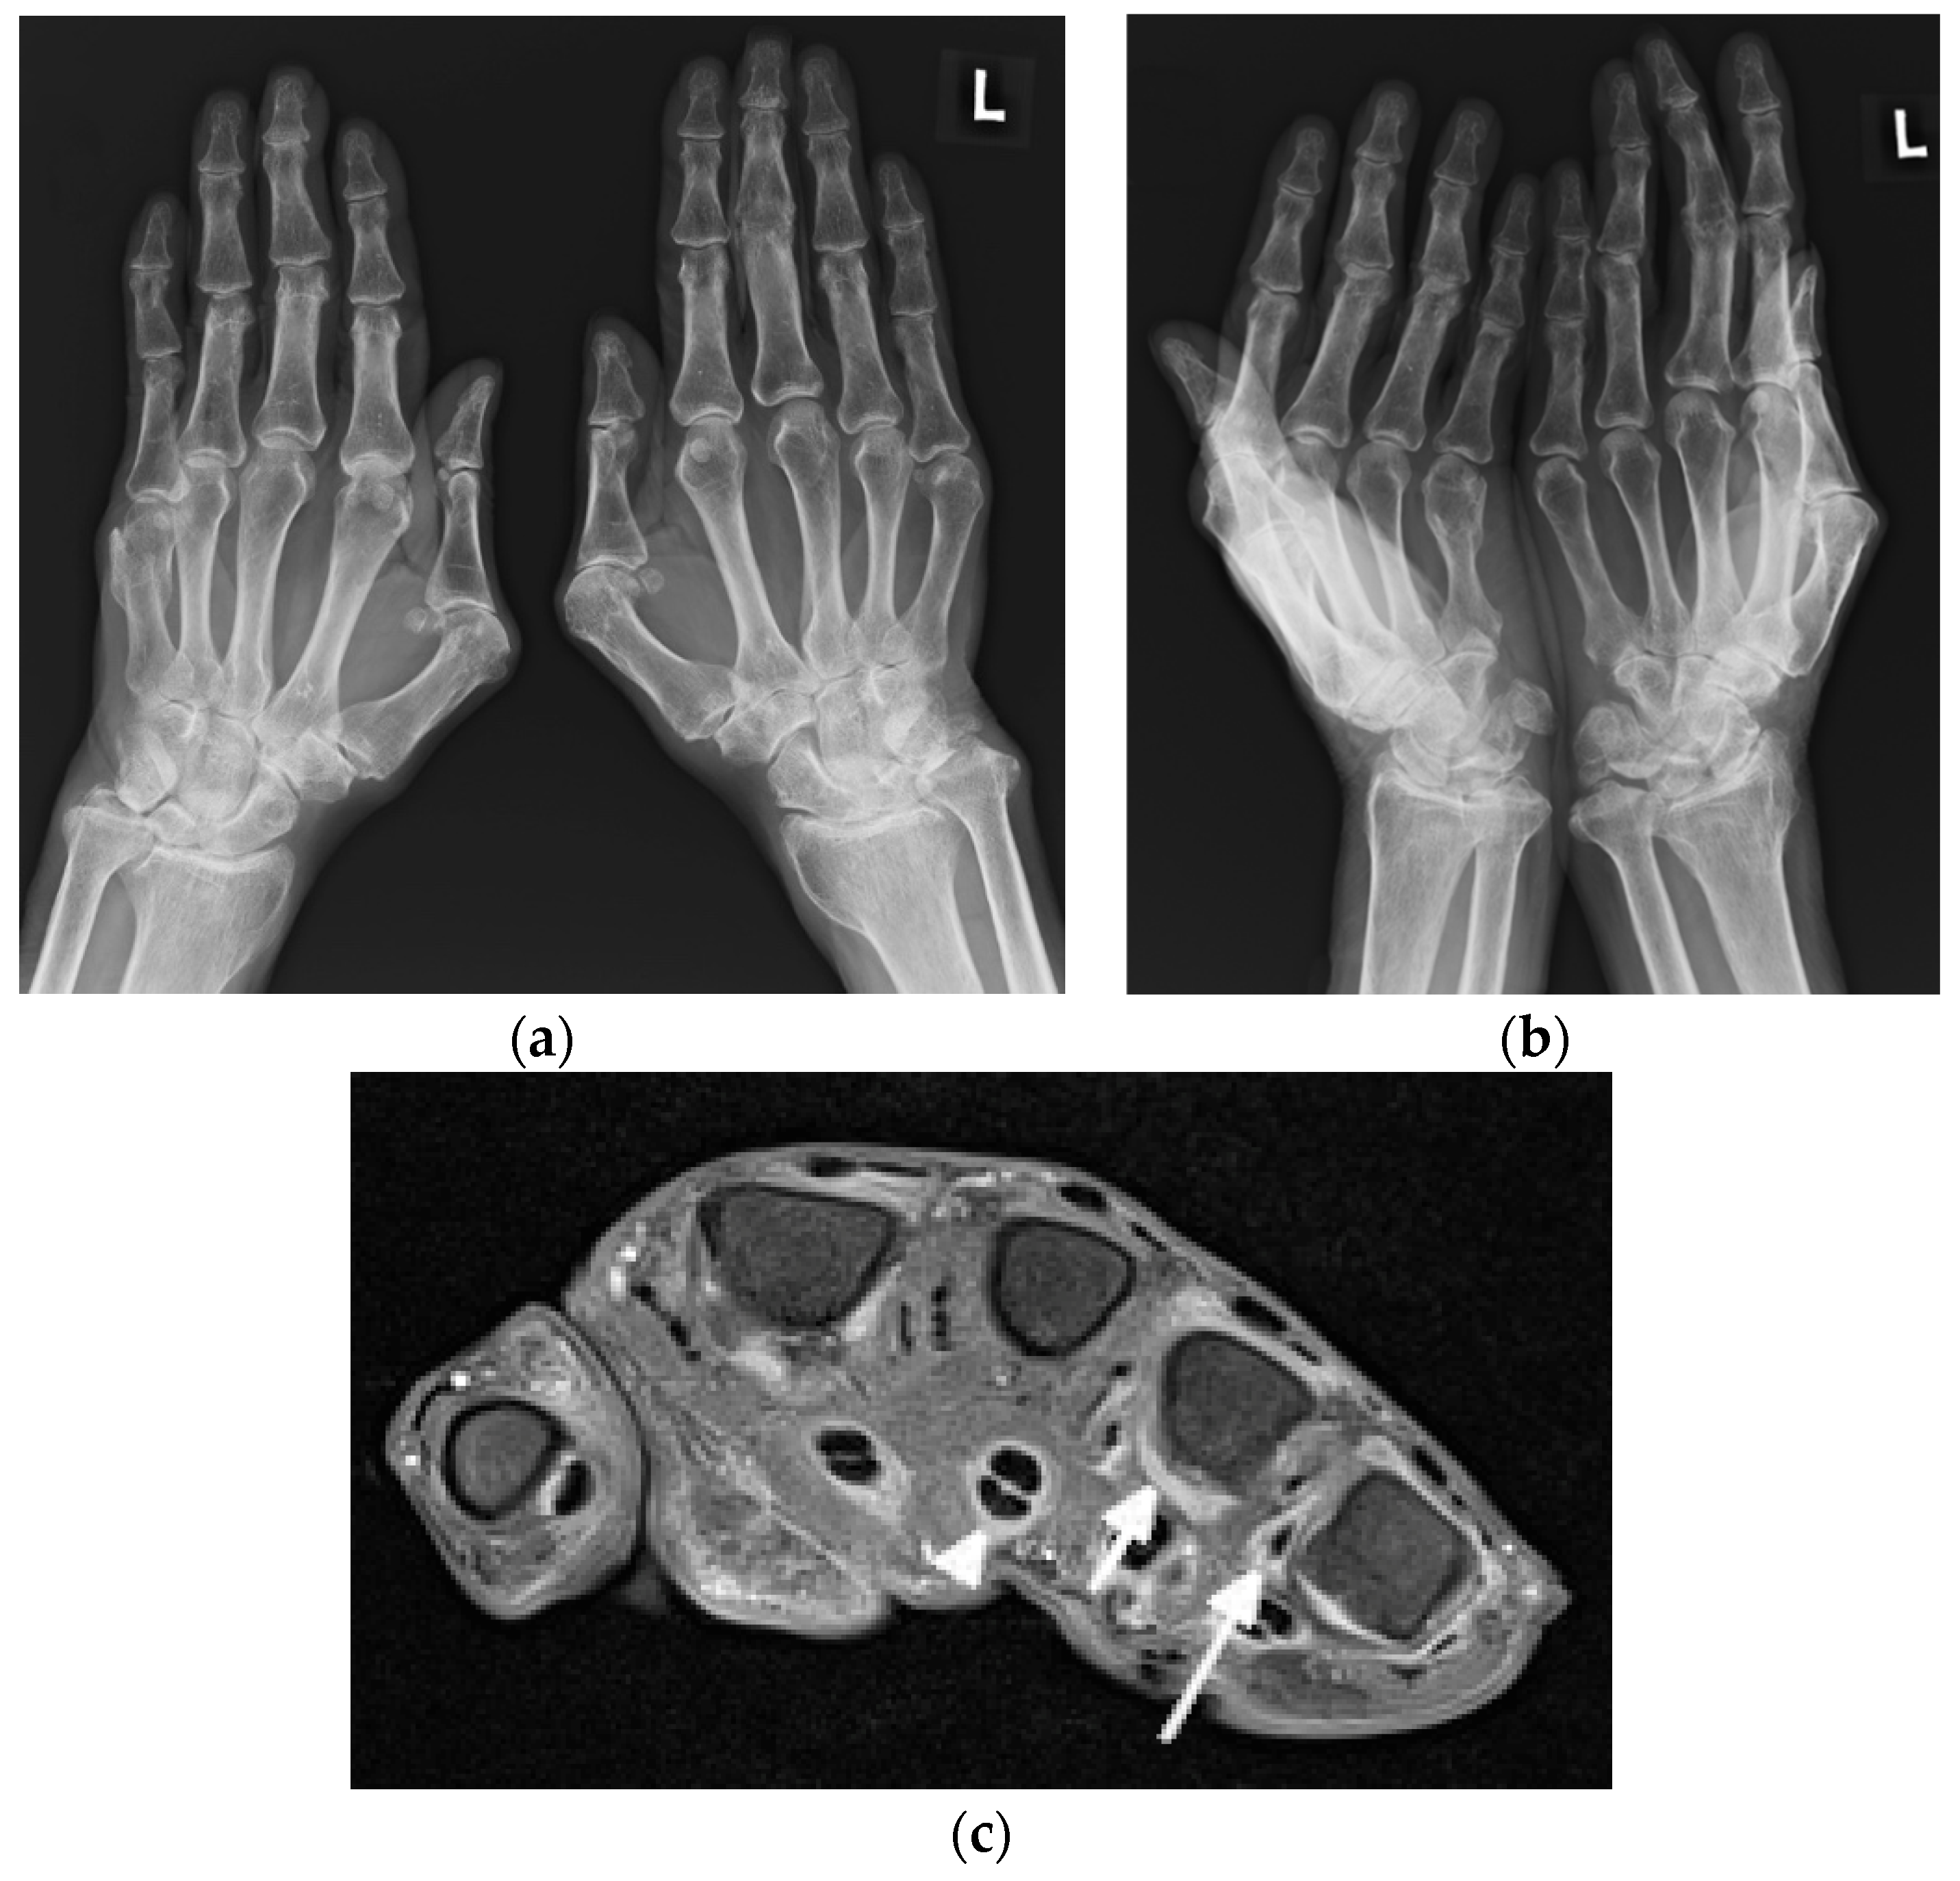

Figure 2.

A 63-year-old male with systemic lupus erythematosus and Jaccoud’s deformities on clinical examination. (a) Posterior–anterior and (b) oblique radiographs of the bilateral hands show ulnar deviation of the lesser finger phalanges of the right hand, with malalignment of the 3rd–5th digits proximal interphalangeal (PIP) joints that are more apparent in (b). They also show contracture at the 3rd PIP joint of the left hand, osteoarthritis of the bilateral wrists and scattering of the metacarpophalangeal (MCP) joints, bilateral positive ulnar variance, and posttraumatic deformities of the bilateral distal radial metaphysis and of the distal right 5th metacarpal. (c) Axial postcontrast T1-weighted magnetic resonance image with fat saturation of the right hand shows MCP joints 2, 4, and 5 synovitis (short arrow pointing to MCP 4), MCP 2, 4, and 5 capsular enhancement (long arrow pointing to MCP 5), and 2–5 flexor tendons tenosynovitis (arrowhead pointing to middle finger flexor tendon sheath).

Figure 4.

A 64-year-old female with SLE diagnosed in 1980 with Jaccoud’s arthropathy for hands and feet. (a) Posterior–anterior and (b) oblique radiographs of the hands show bone demineralization; soft tissue swelling at the wrists; periarticular calcifications; malalignment at the distal radioulnar, radiocarpal, and midcarpal joints; dislocation of the 1st carpometacarpal and subluxation of the 1st metacarpophalangeal joints; and joint space narrowing with cyst-like and erosive/destructive changes consistent with rhupus syndrome. Note the reversible contractures at the proximal interphalangeal joints, apparent in (b) and resolved or less apparent in (a). (c) Anterior–posterior standing radiograph of the bilateral feet and (d) lateral standing radiograph of the left foot show bone demineralization, bilateral hallux valgus deformities, and bilateral 2nd and 3rd hammer toes, as well as a right foot with moderate lateral subluxation.